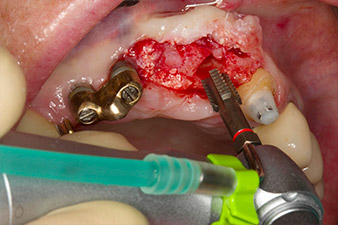

Following primary healing, the soft tissues were shaped using the basally lined bridge. Two months later the site was exposed by a slightly palatal alveolar ridge incision (Fig 2). The dimensions of the alveolar bone proved to be sufficient at position 22. Figures 2 and 4 show the preparation of the implant bed, the tapping and the implantation using Implantmed.

pilot drilling is performed with the new Implantmed and the WS-56 L contra-angle handpiece

Fig. 2: Two months later the pilot drilling is performed with the new Implantmed and the WS-56 L contra-angle handpiece (programme P1, ratio 1:1). The cooling is performed via the spray tube positioned on the left (for right-handed users).